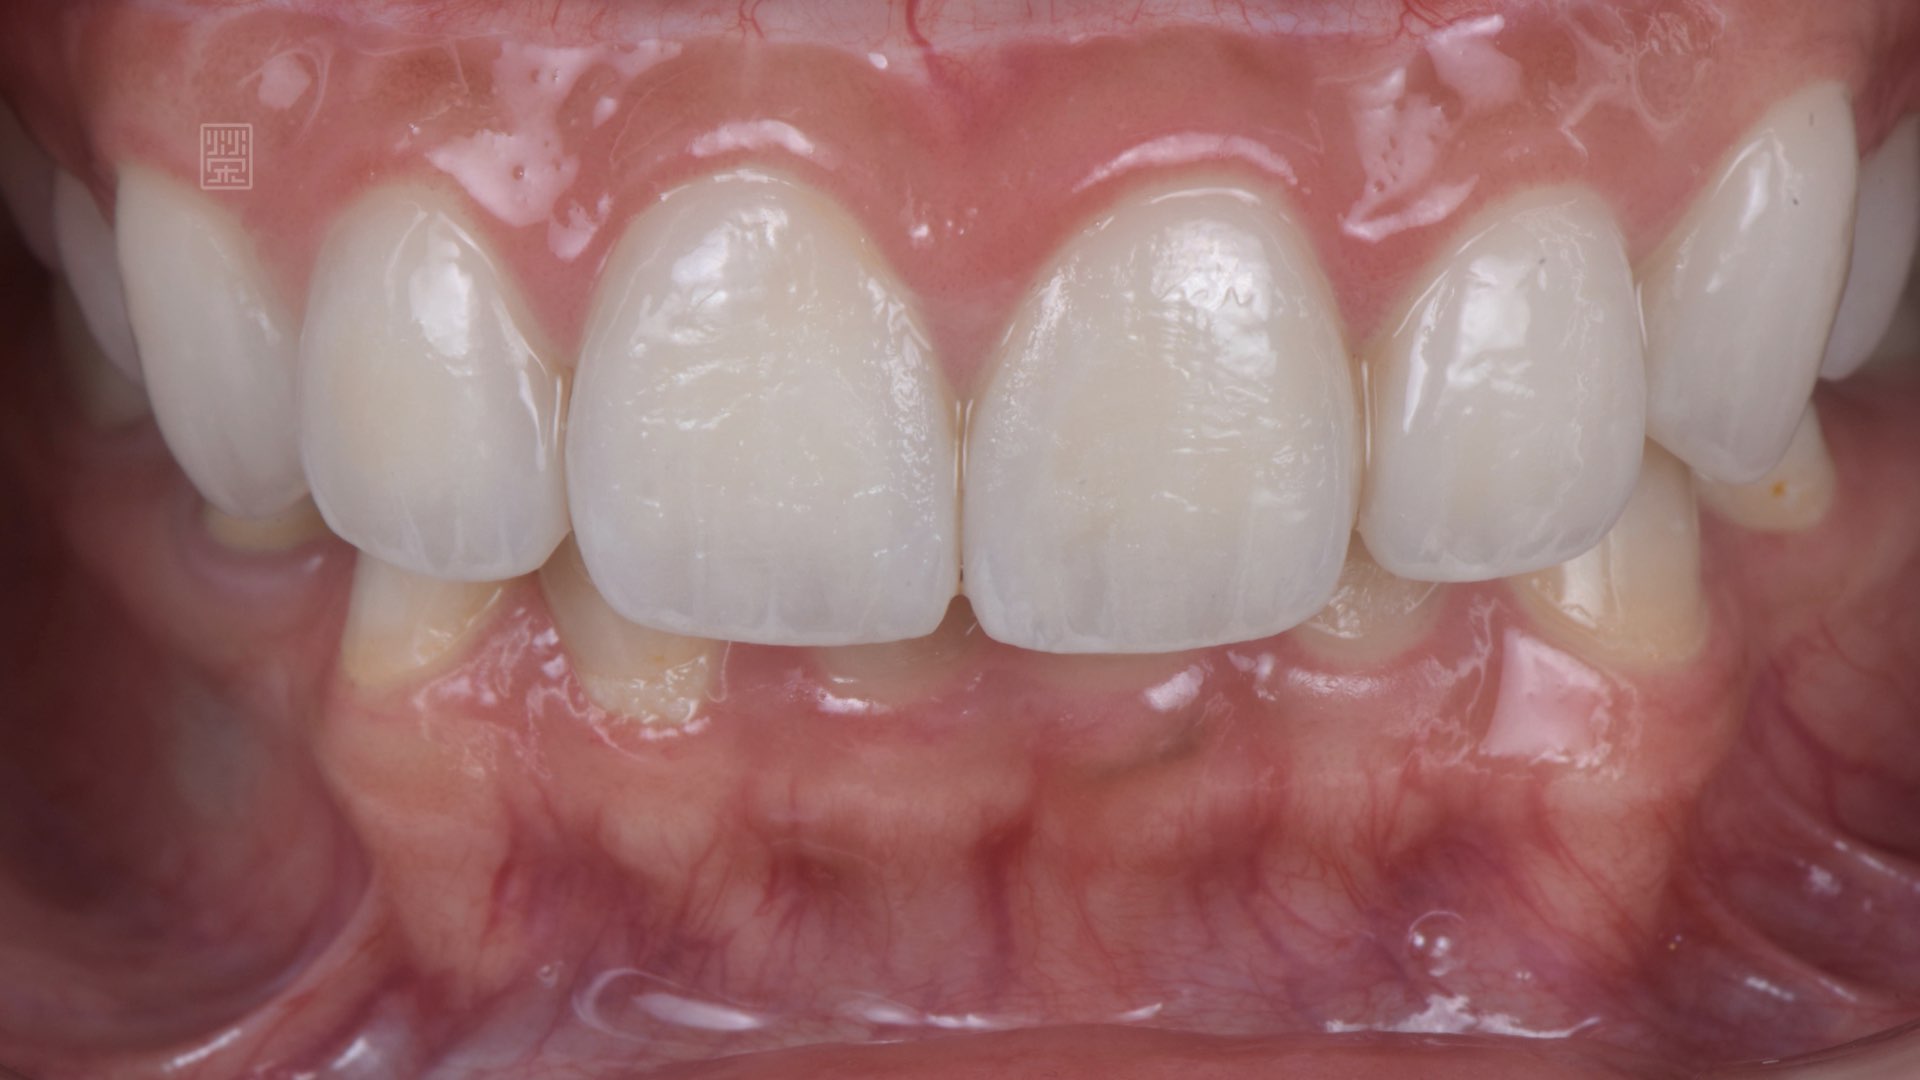

除此之外,陳小姐笑起來的時候,牙齦露出來很多,在開懷大笑時,有點困擾,榮醫師分析後,發現他的牙齒比例位置是蠻正確的,所以用上唇重置術(lip reposition),改善陳小姐笑齦的問題。

經由榮醫師完成療程與陳小姐的配合,不僅恢復陳小姐口腔健康,也能夠讓陳小姐自在地開懷大笑。

笑齦改善

全瓷貼片完成